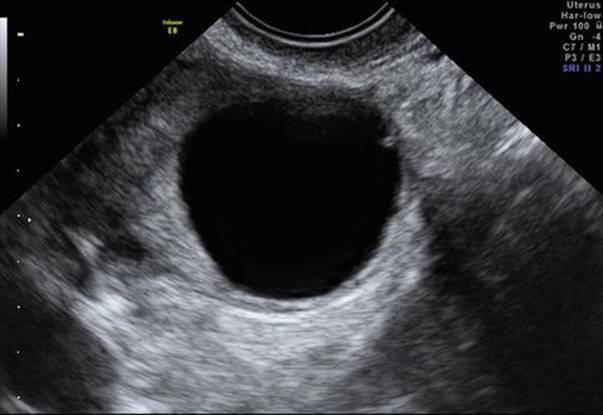

Characteristic ultrasound appearance at the time of ovulation includes diminution in the follicle size or sudden collapse of the follicle, blurring of the follicle borders, which become crenated, and appearance of intrafollicular echoes, which are more isoechogenic with respect to surrounding ovary (Fig. 2.7) and presence of a small amount of free fluid in the pouch of Douglas (POD) (Fig. 2.8). Thereafter, an irregular, slightly cystic structure representing the corpus luteum shrinks throughout the luteal phase of the cycle until luteolysis occurs before menses.

Fig. 2.7

Corpus luteum with increased peripheral blood flow

Doppler in the secretory phase gives an idea about the function of corpus luteum (CL). Usually, the RI of the corpus luteum (Fig. 2.15) is between 0.35 and 0.50. In luteal phase deficiency (LPD), RI is 0.58 ±0.04, PI is 0.70–0.80, and PSV is between 10 and 15.

Fig. 2.15

Doppler of corpus luteum